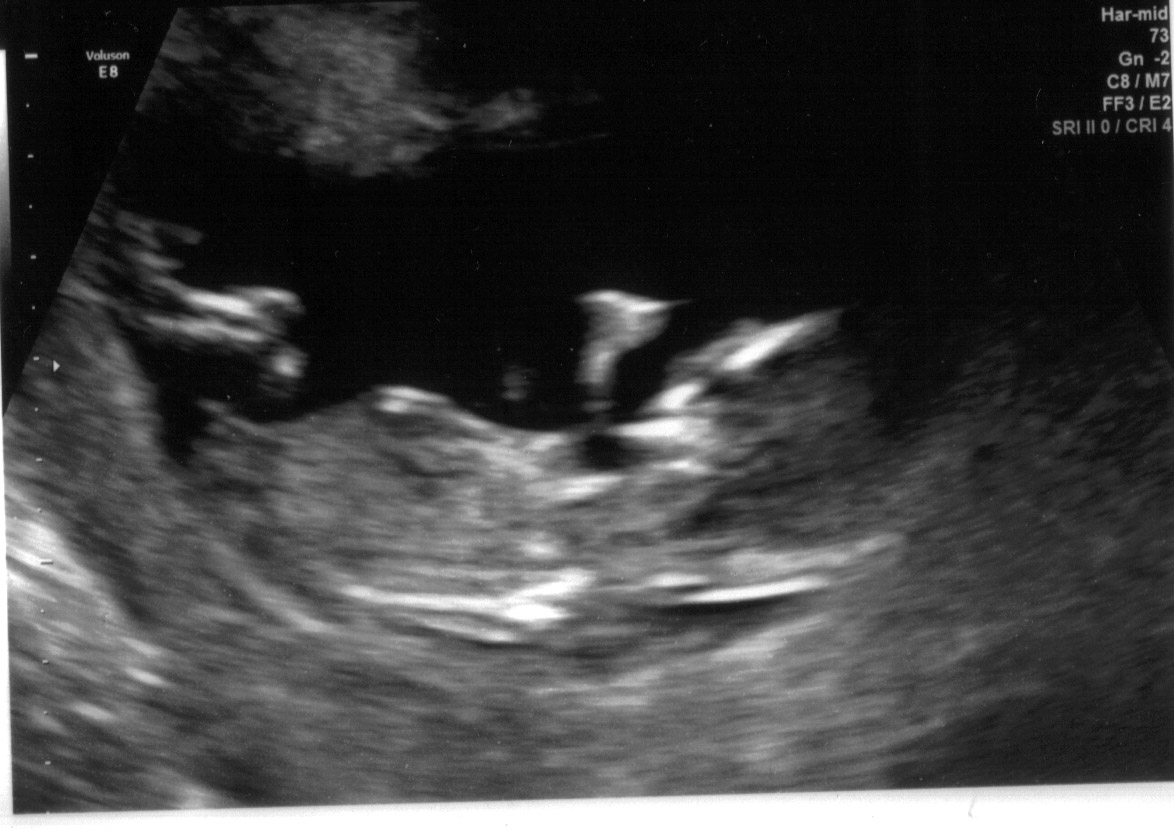

This is my NT scan at 12 weeks. Any guesses on the nub?? Attachment 24079Attachment 24080